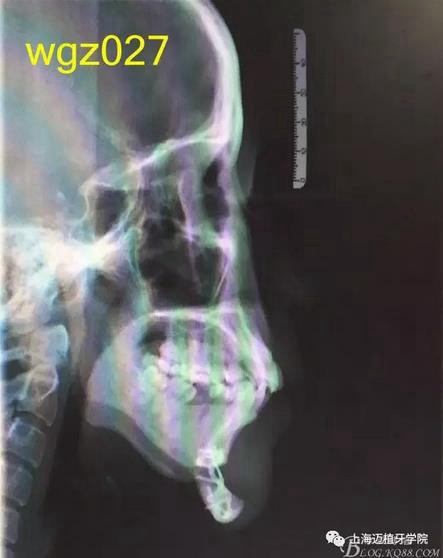

圖2

頭顱側(cè)位片:面型稍凸,上唇在E線前約1.5mm,下唇在 E前約1mm 。

SNA: 85↑ SNB: 75↓ ANB: 10↑ U1-L1: 113.6↓ U1-SN: 107.9

L1-M P: 88 ↓ Y軸角:65.8 FH-MP: 37↑ SN -M P: 45↑